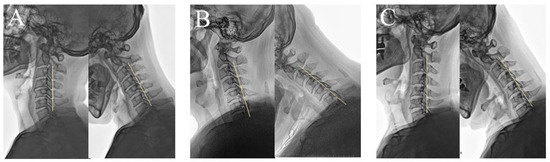

Dynamic K-Line Status and Surgical Outcomes in Multilevel Cervical OPLL: A Multicenter Comparative Study

Background/Objectives: To evaluate the clinical and radiological outcomes of surgical interventions stratified by dynamic K-line status and to identify predictors of neurological recovery in multilevel cervical ossification of the posterior longitudinal ligament (OPLL). Methods: This study analyzed 535 patients with multilevel [...] Read more.

Background/Objectives: To evaluate the clinical and radiological outcomes of surgical interventions stratified by dynamic K-line status and to identify predictors of neurological recovery in multilevel cervical ossification of the posterior longitudinal ligament (OPLL). Methods: This study analyzed 535 patients with multilevel cervical OPLL who underwent anterior cervical discectomy and fusion (ACDF), laminoplasty (LP), or laminectomy with fusion (LF), with a minimum 24 months of follow-up. Patients were classified based on dynamic K-line status—neutral (NK-line) and flexion (FK-line)—into three groups: Group 1 (NK-line [+]/FK-line [+]), Group 2 (NK-line [+]/FK-line [−]), and Group 3 (NK-line [−]/FK-line [−]). Radiographic parameters, JOA scores, and VAS were compared, and multivariate regression identified predictors of recovery. A multinomial inverse probability of treatment weighting (IPTW) analysis was conducted to reduce treatment selection bias. Results: Progressive dynamic K-line negativity was associated with greater cervical kyphosis, a higher canal-occupying ratio, reduced FK-line distance, and poorer neurological recovery. After IPTW analysis, ACDF showed higher adjusted recovery across subgroups. In Group 1, younger age and fewer operative levels predicted better recovery. In Groups 2 and 3, LF demonstrated significantly greater neurological recovery than LP. A larger preoperative FK-line distance and a greater postoperative FK-line distance increase were independent predictors of favorable outcomes. Conclusions: Dynamic K-line stratification has good prognostic value in multilevel cervical OPLL. ACDF remains the most effective procedure across dynamic K-line status groups, and LF is preferred over LP in patients with latent or fixed FK-line (−). Incorporating dynamic K-line metrics into surgical planning could improve procedure selection and enhance neurological recovery. Full article

(This article belongs to the Section Clinical Neurology)